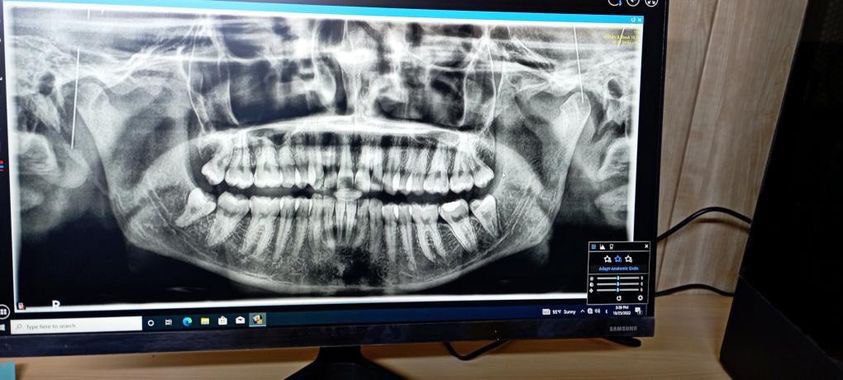

أجراء عملية قلع سن مطمور لمريض في عيادة جراحة الفم